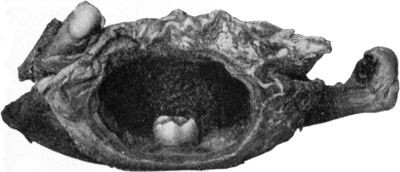

207108.

Advanced Tuberculous Disease of Acetabulum with Caries and Perforation into Pelvis